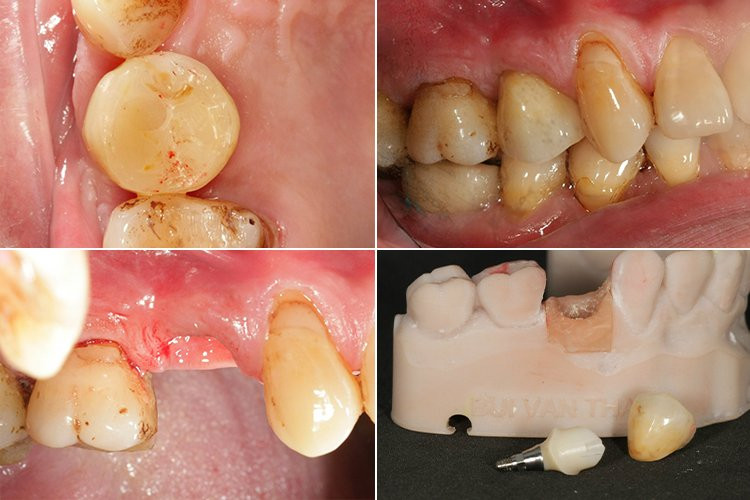

“Nhằm giải quyết triệt để các vấn đề như đọng giắt thức ăn, ánh đen răng sứ và co ngót lợi, kỹ thuật PDR đã sử dụng trụ phục hình (Abutment) cá nhân hóa và răng sứ 3D Pro Multilayer thay thế cho trụ phục hình chế tác sẵn và răng sứ titan.

Abutment cá nhân hóa được gia cố tế bào sinh học tương thích cao bằng công nghệ nano siêu phân tử sẽ giúp nướu sát khít và bám chặt vào cổ Abutment, tạo ra khoảng liên kết sinh học vững chắc như đối với răng thật, ngăn ngừa tình trạng tam giác đen, đọng giắt thức ăn, loại bỏ hoàn toàn nguy cơ viêm nhiễm - nguyên nhân hàng đầu gây đào thải trụ implant.

Răng sứ 3D Pro Multilayer có độ trong mờ hoàn hảo, không nhiễm màu, không bong vỡ và không gây tổn thương các răng đối diện trong quá trình ăn nhai. Do đó, răng sứ được phục hình bằng kỹ thuật PDR sẽ thẩm mỹ nhất và bền vững nhất.”

![]() |

| Abutment cá nhân hoá kết hợp răng sứ 3D Pro Multilayer giúp răng implant tiệm cận sự hoàn hảo |